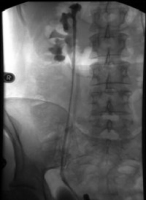

Das retrograde Pyelogramm rechts bestätigte die Diagnose. Es fanden sich zwei getrennte Ostien und in der retrograden Darstellung zwei Ureteren, wobei die distale Harnleiteröffnung zu der

oberen kleinen Niere gehörte

Weigert-Meyersche RegelDer Ureter des unteren Anteils mündet orthotop, der Ureter des oberen Anteils kreuzt den des unteren und mündet kaudal davon.